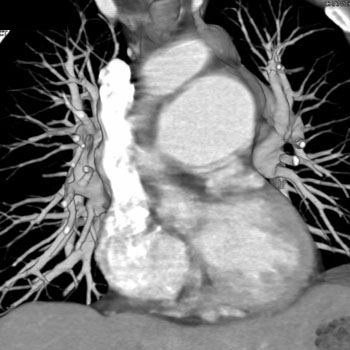

Question 12: 59 year old male with recent onset of chest pain as well as shortness of breath. The patient had a history of “some type of corrective cardiac surgery” as a child. What is the diagnosis?

Diagnosis: Pulmonary Artery Aneurysm